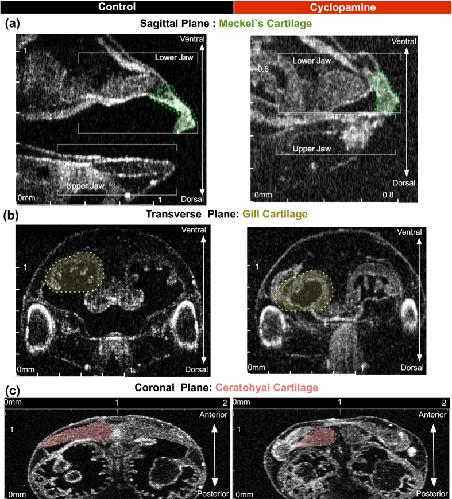

Analysis of Craniocardiac Malformations in Xenopus using Optical Coherence Tomography., Deniz E, Jonas S, Hooper M, N Griffin J, Choma MA, Khokha MK., Sci Rep. February 14, 2017; 7 42506. |

Xenopus Tadpole Craniocardiac Imaging Using Optical Coherence Tomography., Deniz E, Mis EK, Lane M, Khokha MK., Cold Spring Harb Protoc. June 7, 2022; 2022 (5): Pdb.prot105676. |